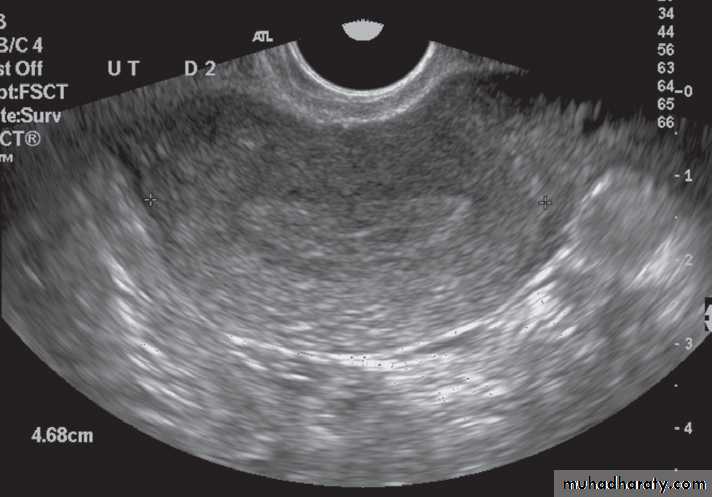

-The typical features of

polycystic ovaries on

ultrasound or MRI include

large volume ovaries

with multiple small

follicles arranged

around the periphery,

forming the appearance

of a ‘string of pearls’ .